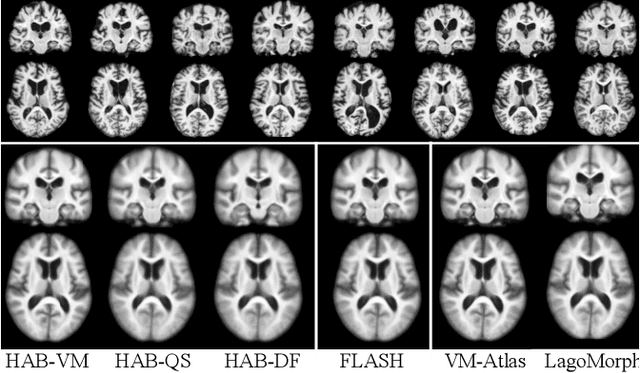

Abstract:Registration-based atlas building often poses computational challenges in high-dimensional image spaces. In this paper, we introduce a novel hybrid atlas building algorithm that fast estimates atlas from large-scale image datasets with much reduced computational cost. In contrast to previous approaches that iteratively perform registration tasks between an estimated atlas and individual images, we propose to use learned priors of registration from pre-trained neural networks. This newly developed hybrid framework features several advantages of (i) providing an efficient way of atlas building without losing the quality of results, and (ii) offering flexibility in utilizing a wide variety of deep learning based registration methods. We demonstrate the effectiveness of this proposed model on 3D brain magnetic resonance imaging (MRI) scans.